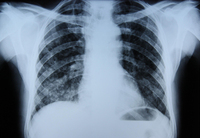

Radiografía de tórax que muestra una adenopatía hiliar bilateral en un paciente con sarcoidosis

De la colección personal del Dr. M.P. Muthiah, Departamento de Medicina Intensiva y Pulmonar y Medicina del Sueño, University of Tennessee